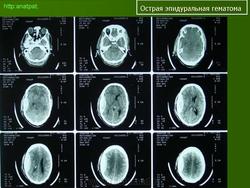

1. КТ головного мозга пациента с двухсторонними эпидуральными гематомами.